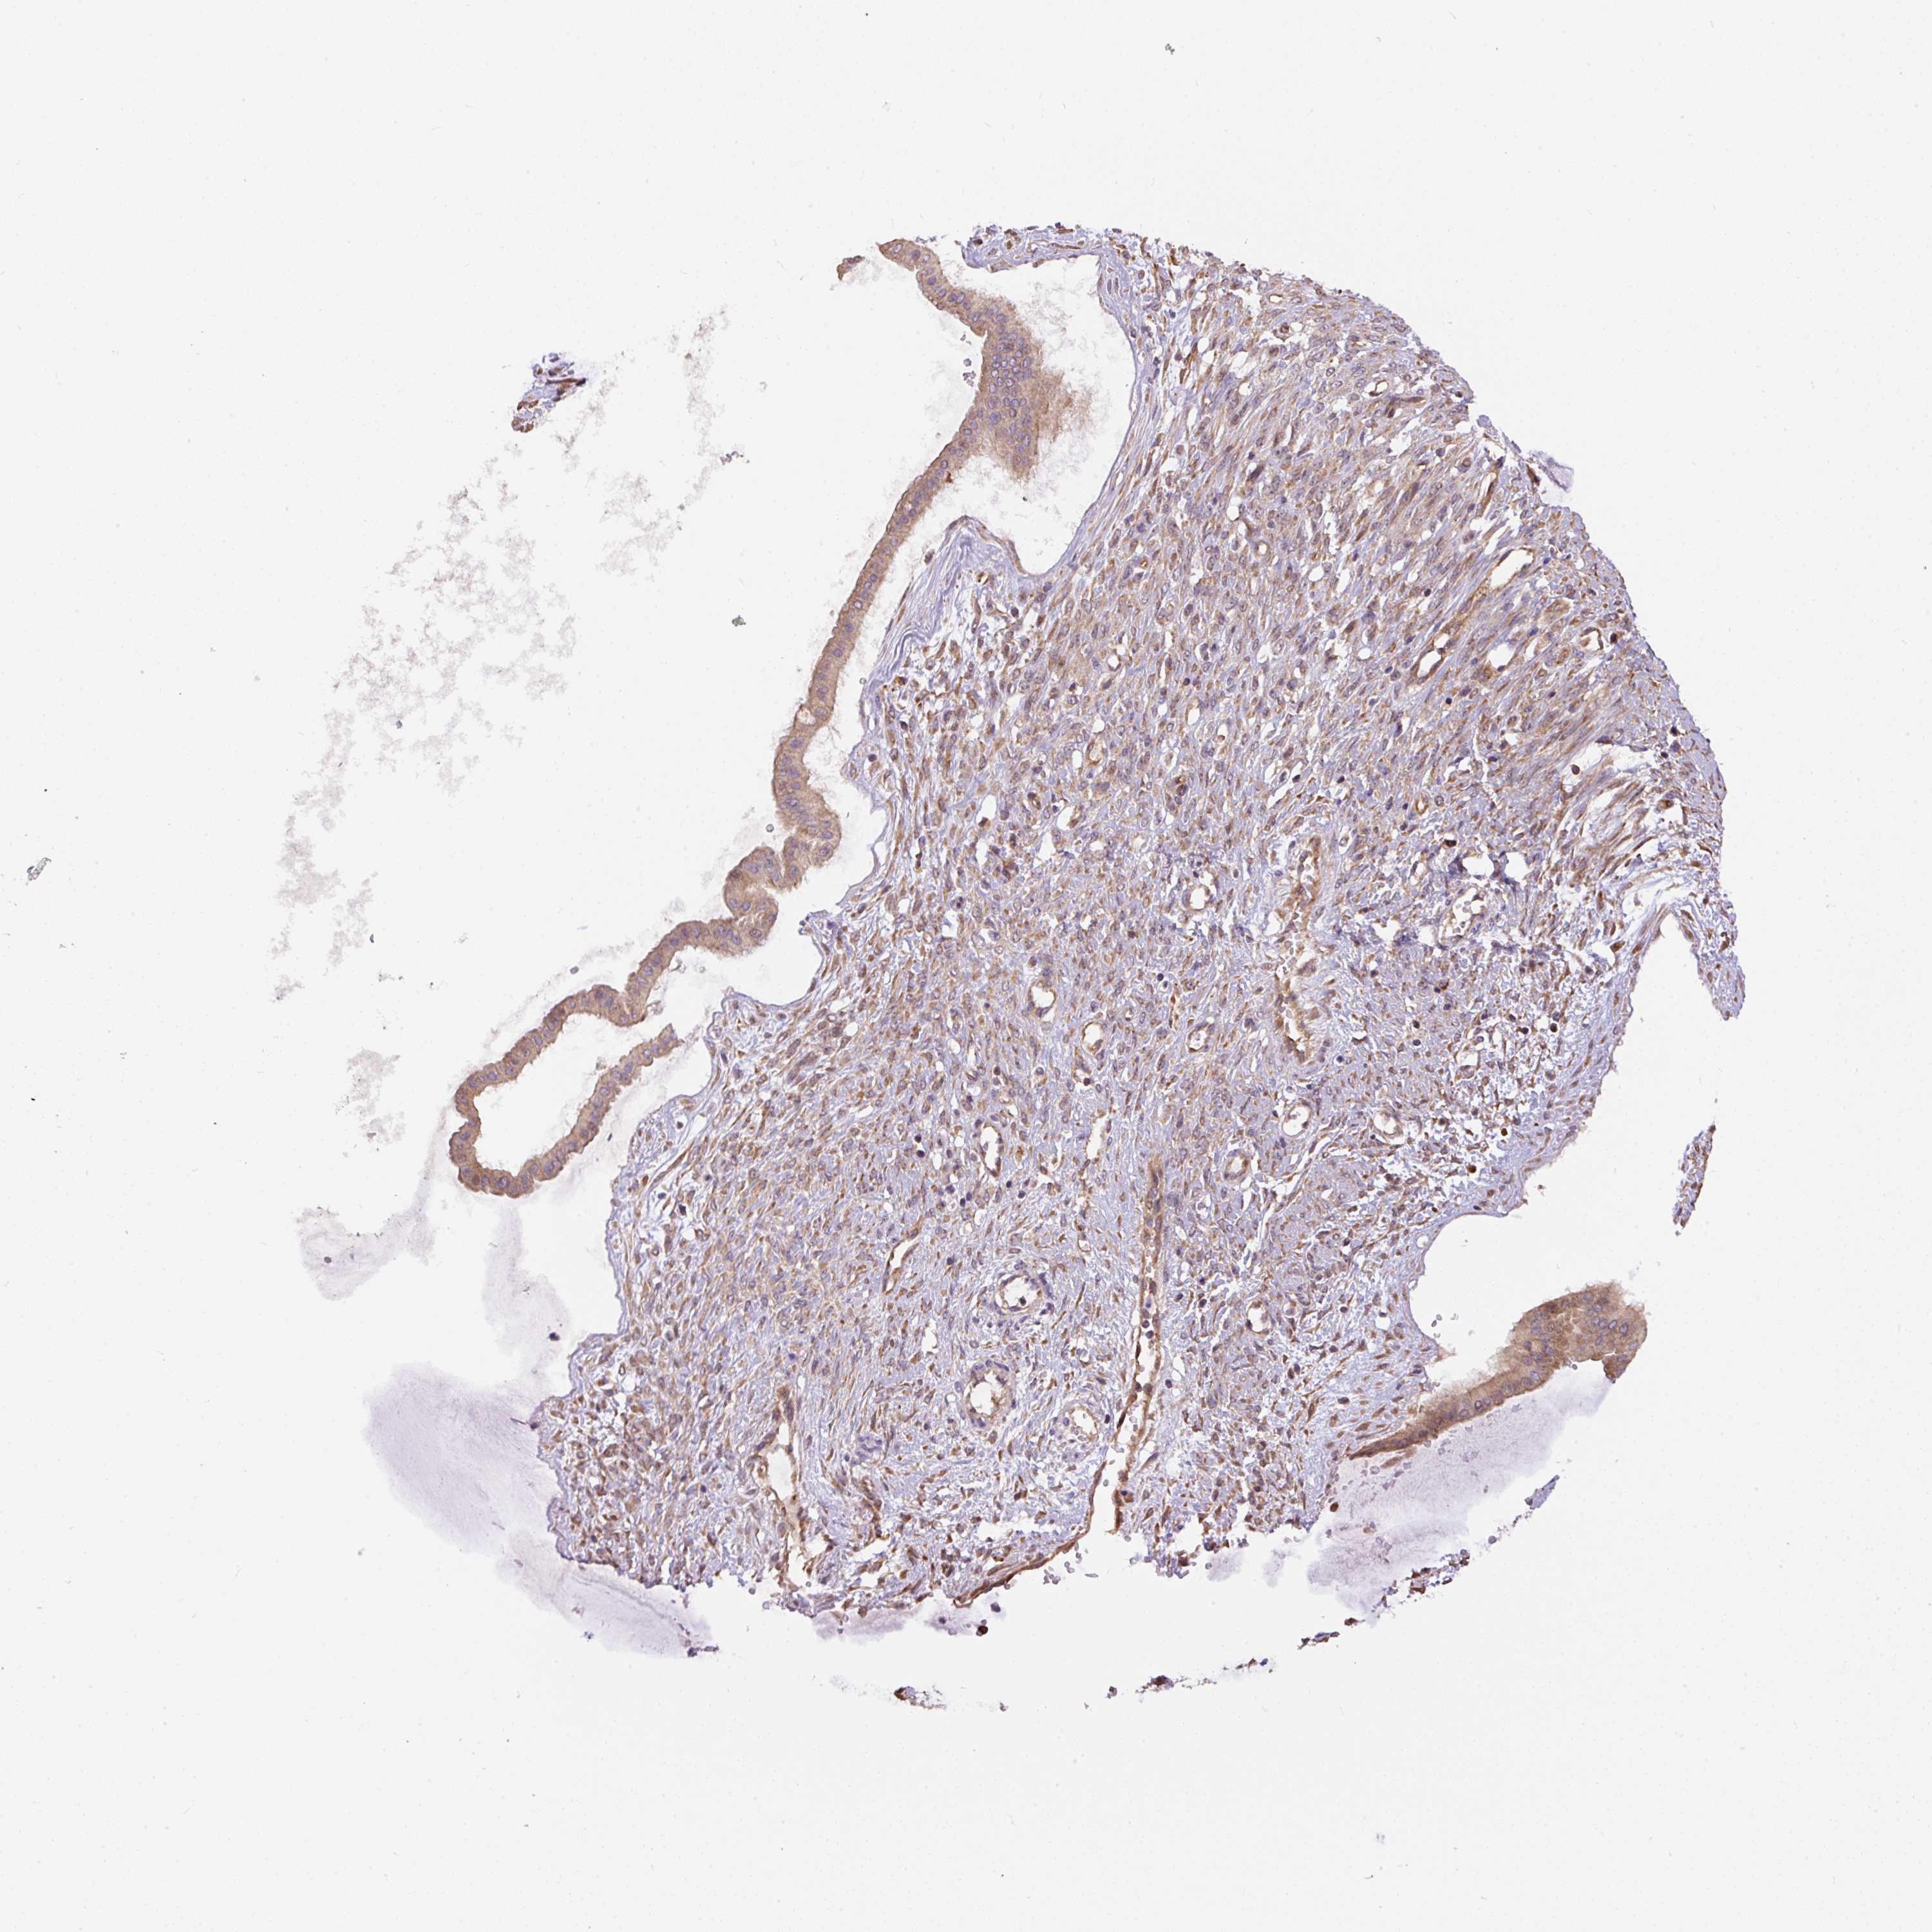

OVARIAN CANCER - Protein expressioni

A mouse-over function shows sample information and annotation data. Click on an image to view it in a full screen mode. Samples can be filtered based on level of antibody staining by selecting one or several of the following categories: high, medium, low and not detected. The assay and annotation is described here.

Note that samples used for immunohistochemistry by the Human Protein Atlas do not correspond to samples in the TCGA dataset.

Antibody stainingi

Antibody staining in the annotated cell types in the current human tissue is reported as not detected, low, medium, or high, based on conventional immunohistochemistry profiling in selected tissues. This score is based on the combination of the staining intensity and fraction of stained cells.

Each image is clickable and will lead to virtual microscopy that enables deeper exploration of all samples and also displays staining intensity scores, fraction scores and subcellular localization as well as patient and tissue information for each sample.

Antibody HPA043900

Antibody CAB004541

Staining

High

Cystadenocarcinoma, serous, NOS

Carcinoma, NOS

Cystadenocarcinoma, mucinous, NOS

Carcinoma, endometroid